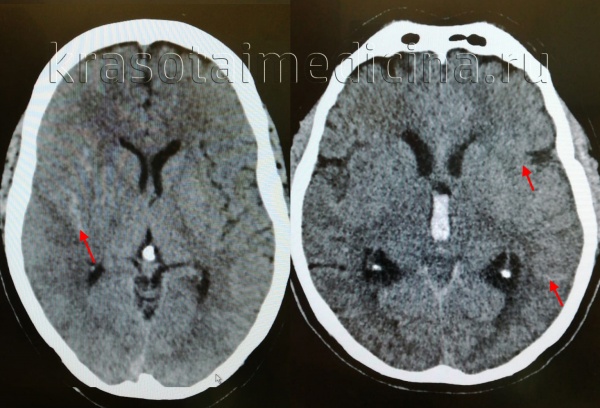

КТ головного мозга. Геморрагический инсульт, обширная интрапаренхиматозная гематома в левой гемисфере

Они позволяют определить объем и локализацию внутримозговой гематомы, степень дислокации мозга и сопутствующего отека, наличие и область распространения кровоизлияния. Желательно проведение повторных КТ-исследований, чтобы проследить эволюцию гематомы и состояние мозговой ткани в динамике.